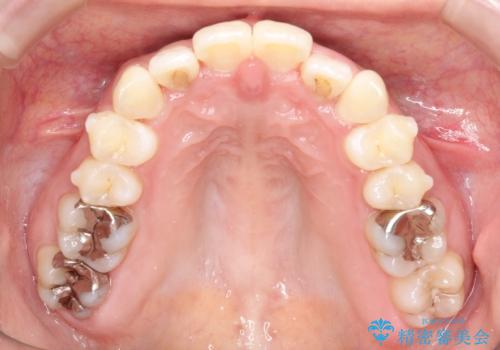

初診時の歯並びの状態としては、上下ともに前歯部の中等度のがたつきがあり、特に左上の前歯が1本内側に入り込んでしまっている状態でした。

また、2mm程度の正中離開がありました。

内側に入り込んでしまっている歯を出してくることに非常に時間がかかりましたが、一度歯を歯茎の方へ押し込みそして前へ出してくる2段階の治療を行いました。